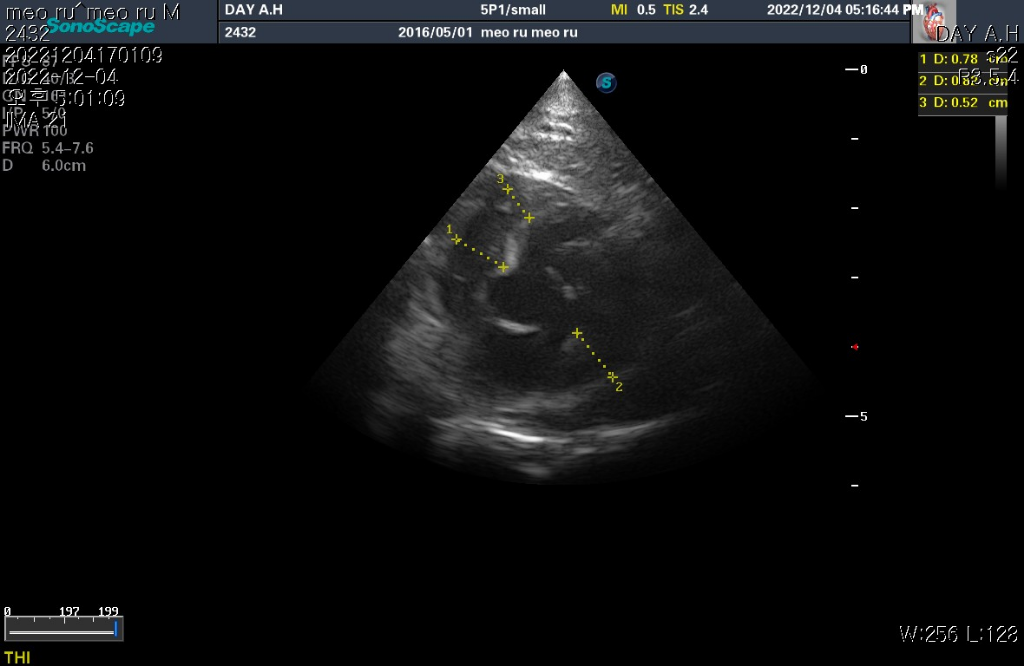

하지만 심장 질환의 잠정적 확진 golden standard는 심장 초음파 검사로 심장 초음파 검사상 심장의 벽 구조가 6mm이상이라면 HCM의 가능성이 매우 높다고 판단합니다.

현재 첨부한 사진상에서 6mm이상의 직경을 보이는 사진들이 존재하기 때문에 해당 검사를 진행한 수의사의 기준상 HCM의 가능성이 높다고 판단하는것은 합리적입니다.